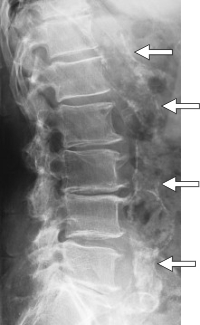

Verdünnung der Gefäss-Innenwand nach 30 Chelattherapien

IM T re / li = Messungen vor Therapie

re / li n. = Messungen nach Therapie

0 = Durchschnittswerte

Die Ergebnisse sind hochsignifikant.